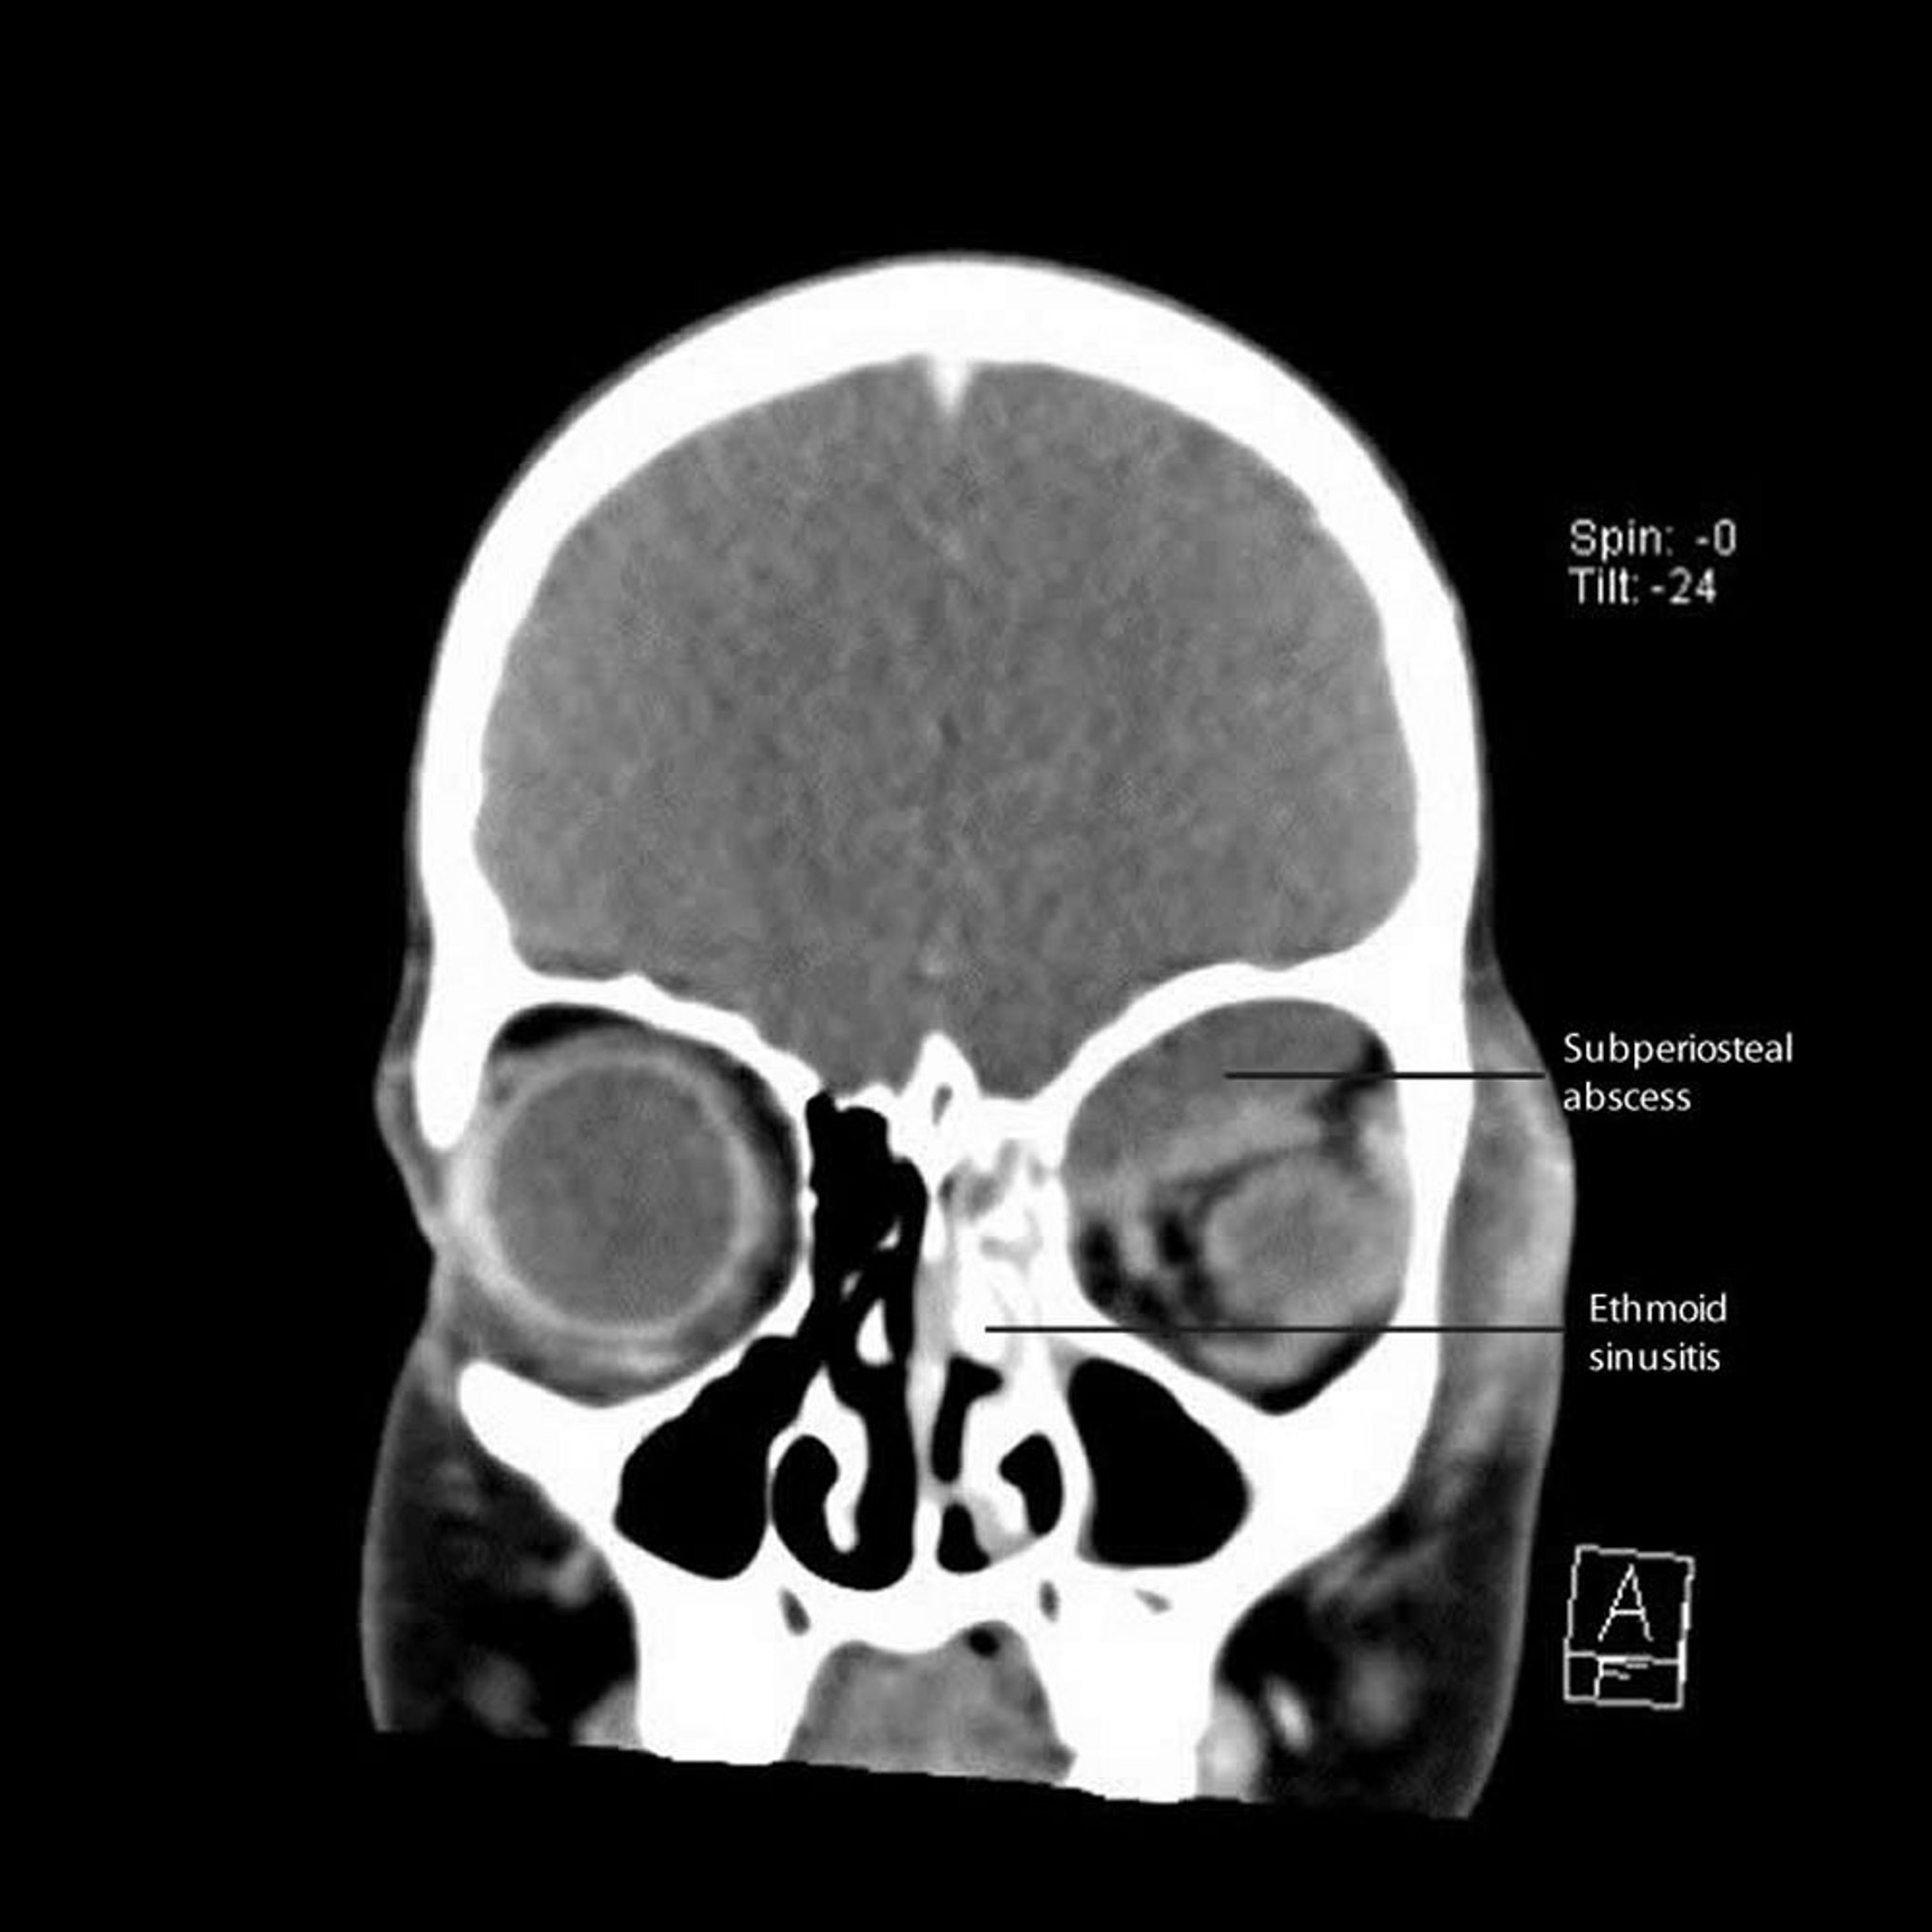

Sinusite ethmoïdale avec abcès sous-périosté

Cette TDM montre une sinusite ethmoïdale gauche avec un abcès sous-périosté adjacent situé le long de la paroi interne et du toit de l'orbite.

CT courtesy of James Garrity, MD.